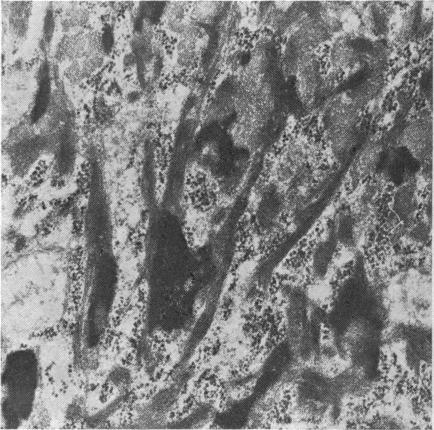

The morphology of the keratinizing epithelia in the mouth is reviwed in the light of recent knowledge. There appears to be a spectrum of degrees of keratinization rather than distinct types, and a degree of keratinization is reflected in the degree of packing and orientation of tonofilaments. The role of keratohyaline and other granules in the process is discussed and it is suggested that modification of the cell membrane is an important part of keratinization. Although the potential of the various areas in the mucosa is genetically determined and appears early in fetal life, the connective tissue exerts an influence on the extent of keratinization of the surface in a manner which is not understood.

根据最新知识,对口腔中角化上皮的形态进行了综述。角化程度似乎存在一个连续谱,而非不同类型,角蛋白丝的聚集和排列程度反映了角化程度。文中讨论了透明角质颗粒及其他颗粒在此过程中的作用,并提出细胞膜的修饰是角化的重要组成部分。尽管黏膜各区域的潜能由基因决定且在胎儿期早期就已显现,但结缔组织以一种尚不清楚的方式影响着表面的角化程度。